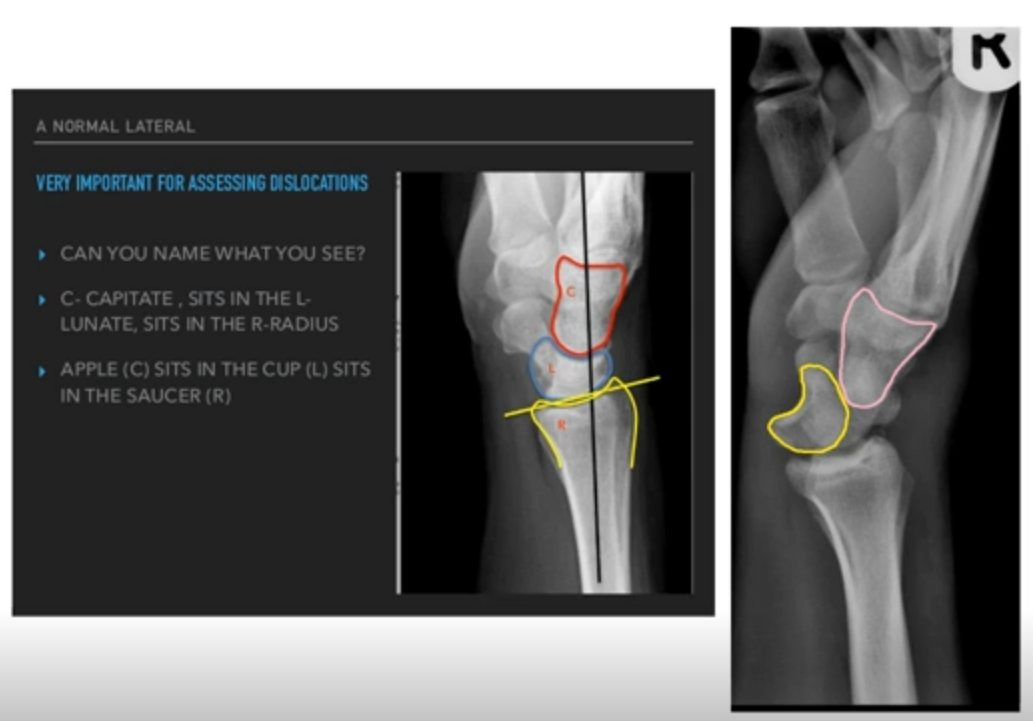

• Wrist Sprains - scapholunate ligament injury:

• Scapholunate ligament is important for carpal stability - chronic scapholunate deficiency leads to instability